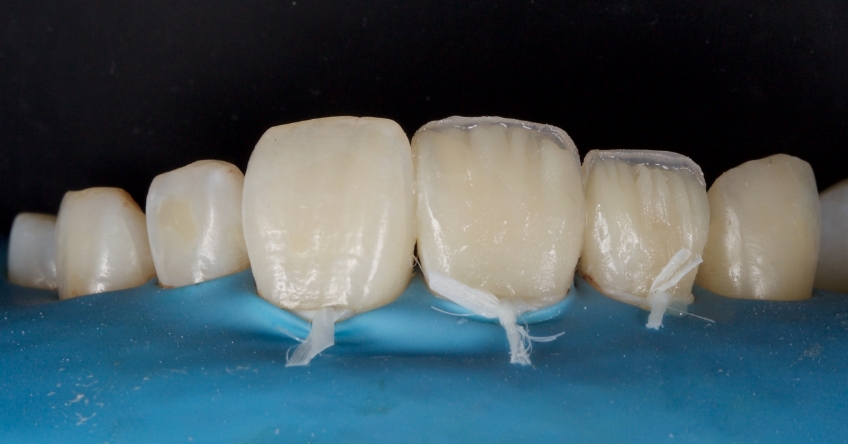

Any biofilm and aprismatic enamel were removed from the tooth, and the fragment was fragmented with light hydro abrasion with 29-micron alumina at 2-3 bar pressure. The tooth and the fragment were etched with 37% phosphoric acid (Ultradent), and a fourth-generation dentin bonding agent (Kerr, OptiBond FL) was applied (the adhesive component was not light-cured).

The fragment was luted to the tooth with heated chromatic enamel shade composite (GC G-aenial A2 shade). The heater used was a Calset Warmer from Addent. The excess composite was cleaned with an interproximal carver from American Eagle and smoothed with a number three brush and modeling resin (Brush & Sculpt from Cosmedent).

The composite was heated because it gained lower viscosity to improve adaptation. Plus, heating increases the conversion of monomer to polymer, which improves the physical characteristics of the resin, such as flexural strength and wear resistance, according to research by Da Costa, Hilton, and Swift in 2011.

The resin was polymerized, and the oxygen-inhibited layer was removed by polymerization under glycerine.